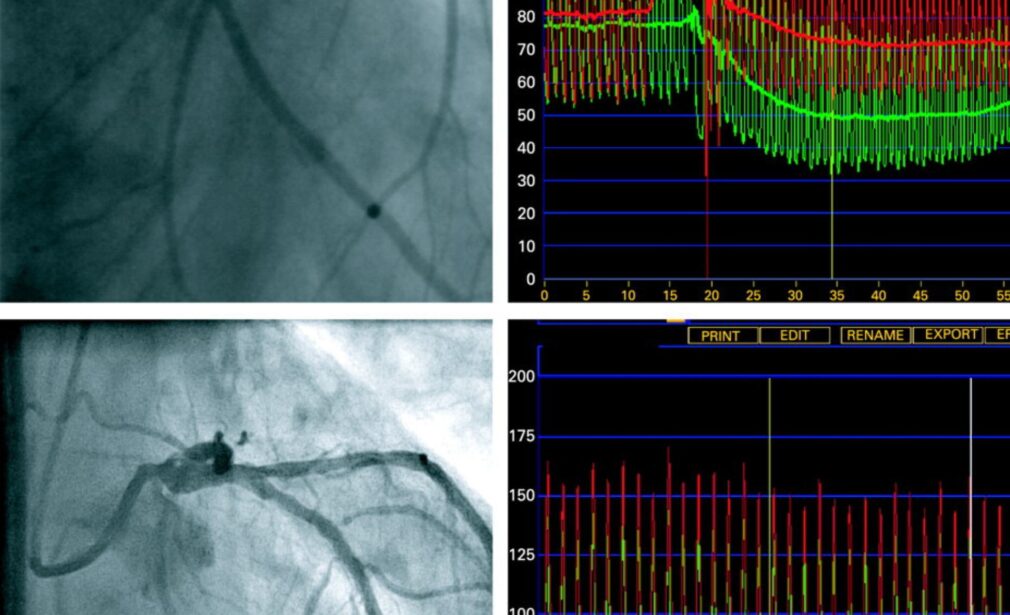

FFR is a measurement of the pressure differences across a narrowed section of a coronary artery. Unlike traditional angiography, which shows only the visual narrowing, FFR reveals whether that narrowing is actually restricting blood flow to the heart muscle.

An FFR value of 0.80 or lower usually means the blockage is significant enough to warrant PCI (stent placement). By using this data, Dr. Honey Sharma can make informed decisions about which lesions to treat, avoiding unnecessary interventions.

Step 4: FFR Measurement

The device calculates the ratio of blood pressure before and after the narrowing.

If the FFR reading is ≤ 0.80, the lesion is significant and PCI (stenting) is performed immediately. If not, medical management may be advised instead.